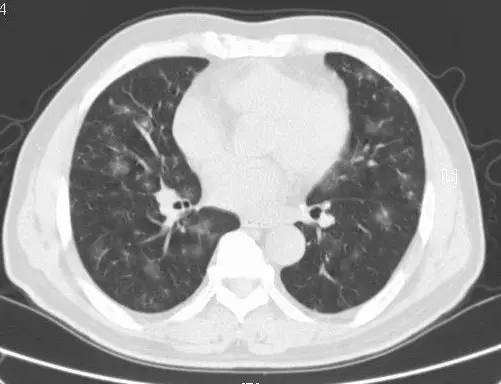

病例二(来自北京大学学报在 2008 年个案报道)

基本病史:患者女性,34 岁,间断性咳嗽、咯血伴气短 10 年,加重 2 周。患者 10 年前受凉后出现咳嗽、咳痰,痰中带血,伴有胸闷气短,严重时出血口唇紫绀。行影像学检查结果如下:

图 2 胸部 X 线正位片显示双肺弥漫分布的细小结节影,以双下肺为著,右侧较左侧重,左肋膈角变钝;胸部 CT 结果显示双下肺方腺泡样小结节影,右中叶可有。最终病理诊断结果为特发性肺含铁血黄色沉着症